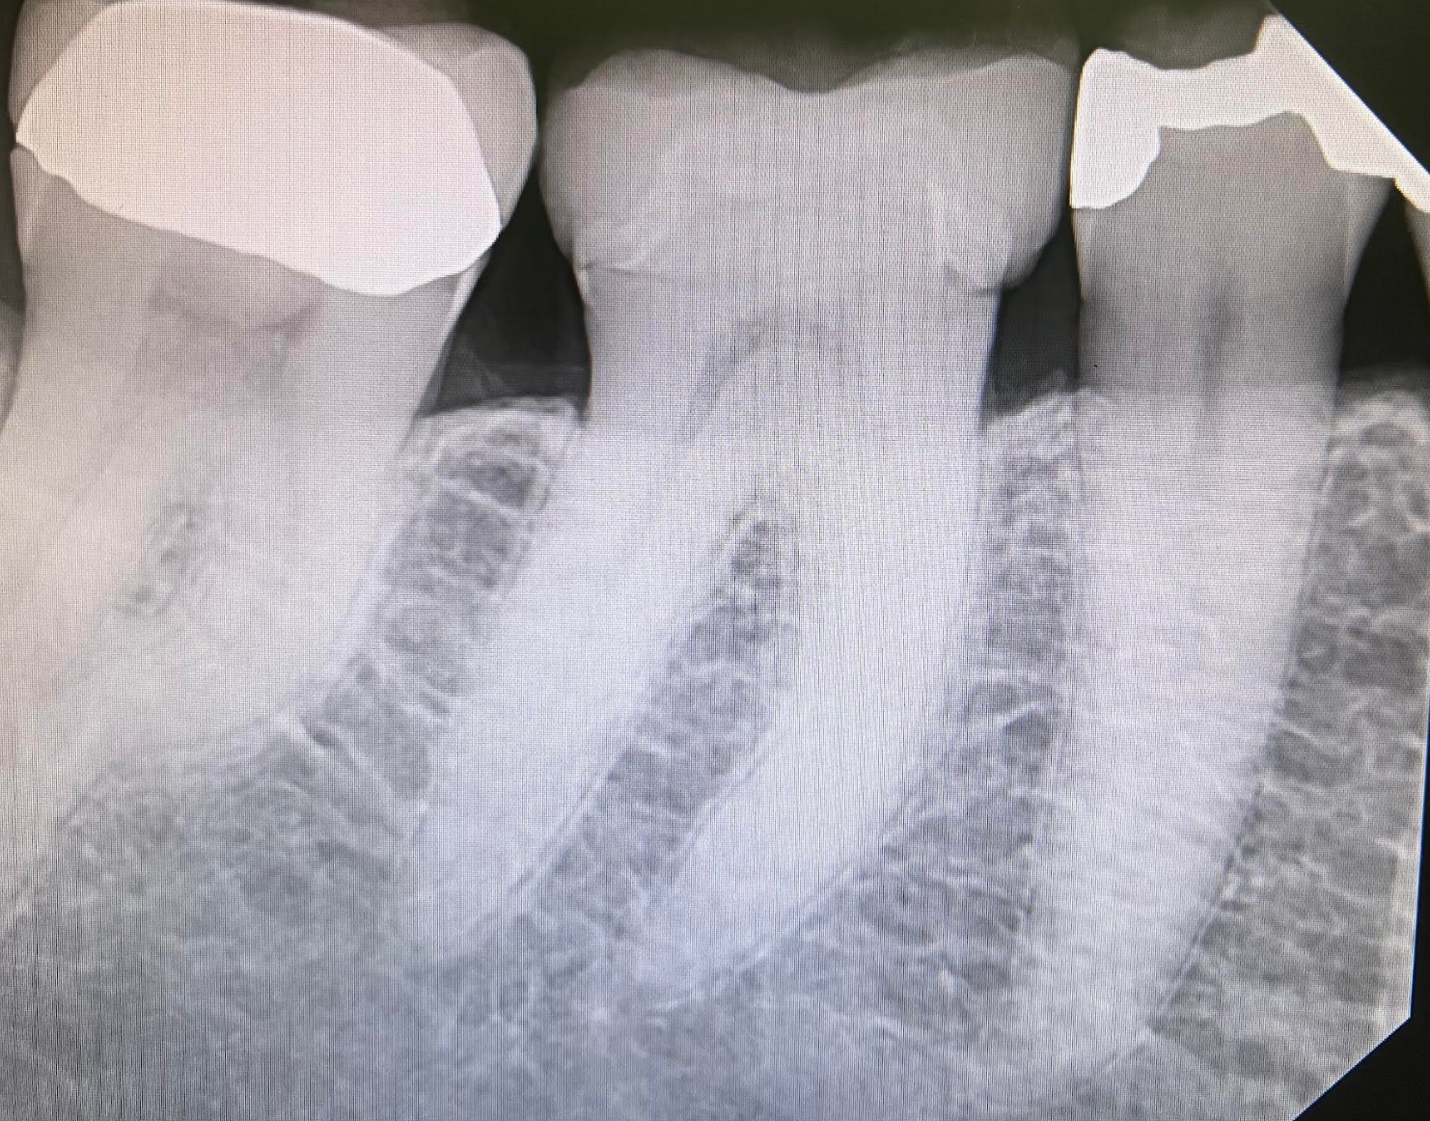

Example 3: Increasing case acceptance for a new patient

The last example I want to show is one that I really think highlights the power of Overjet. As Imagen doctors we all are aware of how technology and state of the art treatment can be a very powerful marketing tool for our practice, and Overjet is no different. Here we had a new patient to our practice, which in my opinion is the hardest patient to get to accept treatment as we haven’t had much time to establish trust. This was also a new patient who did not report having any issues and was just in for a prophy as she moved from out of town:

Our policy is to have the hygiene assistant seat patient, take X-rays, put any relevant photos on the tv screen in front of the patient (this would be any red from Overjet basically) and then bring it to the hygienists attention when she comes into the room so the patient can hear. Typically a hygiene assistant would have no idea about anything related to treatment, but with overjet she can tell the hygienist to look at teeth 30 and 31:

The hygienist now will have a focus on 30 and 31 when performing the prophy – and the patient is now engaged and expecting to hear about that area. Due to the hygienist focusing on these areas she noted that she had an explorer stick on the mesial margin of crown #30, but not #31. She informed the patient and by the time I came in, it had been the patients 4th time hearing about the need for a crown on tooth #30. Due to the clinical exam and the fact this was the first time we were seeing the patient we elected to place a watch on tooth #31 which the patient appreciated.

As countless studies have shown, a patient needs to hear about a treatment at least 3 times before they remember it and are motivated to treat it. With Overjet we were able to show a new patient the need for a crown with immediate acceptance and trust. Not only that, she commented several times on how impressive that we were so “state of the art”.